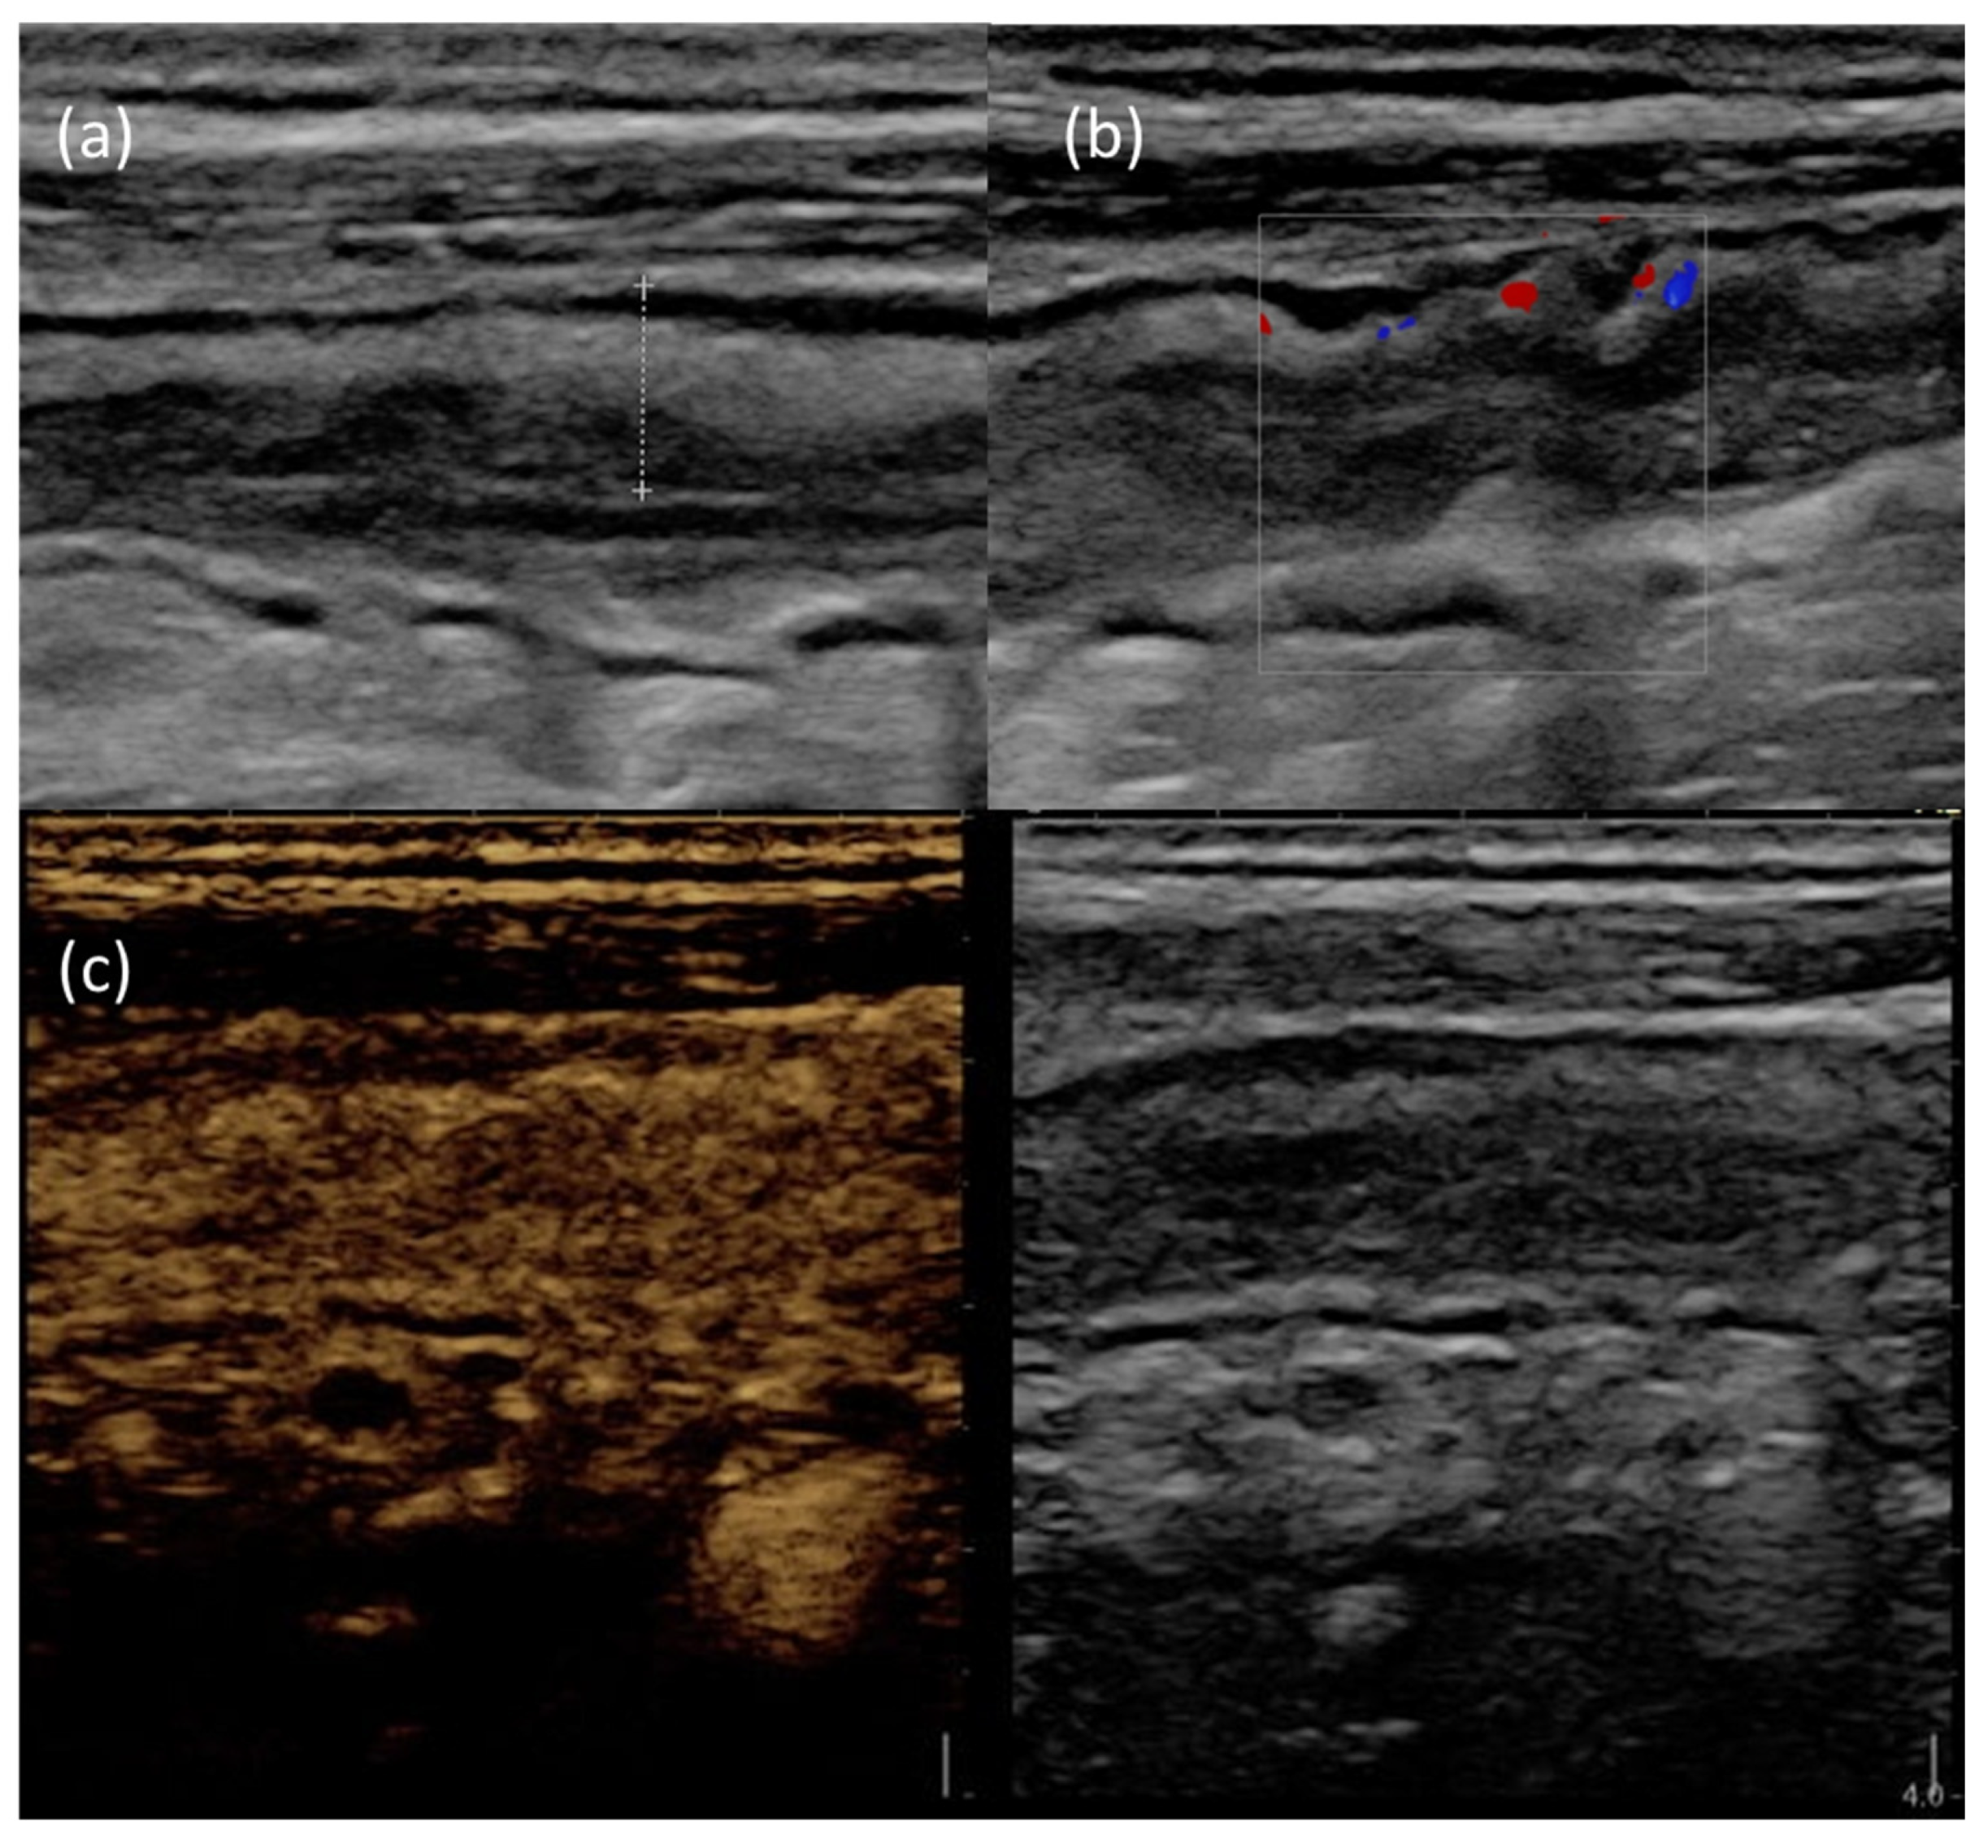

Figure 3 provides an example of IUS images showing ultrasonographic parameters of disease activity.

Figure 3.

IUS images of the terminal ileum in a patient with active CD. (a) B-mode IUS showing increased BWT (dotted line) with preserved wall stratification. (b) The use of color doppler highlights increased intramural vascularization. (c) After Sonovue® injection, the affected bowel wall shows increased contrast enhancement.